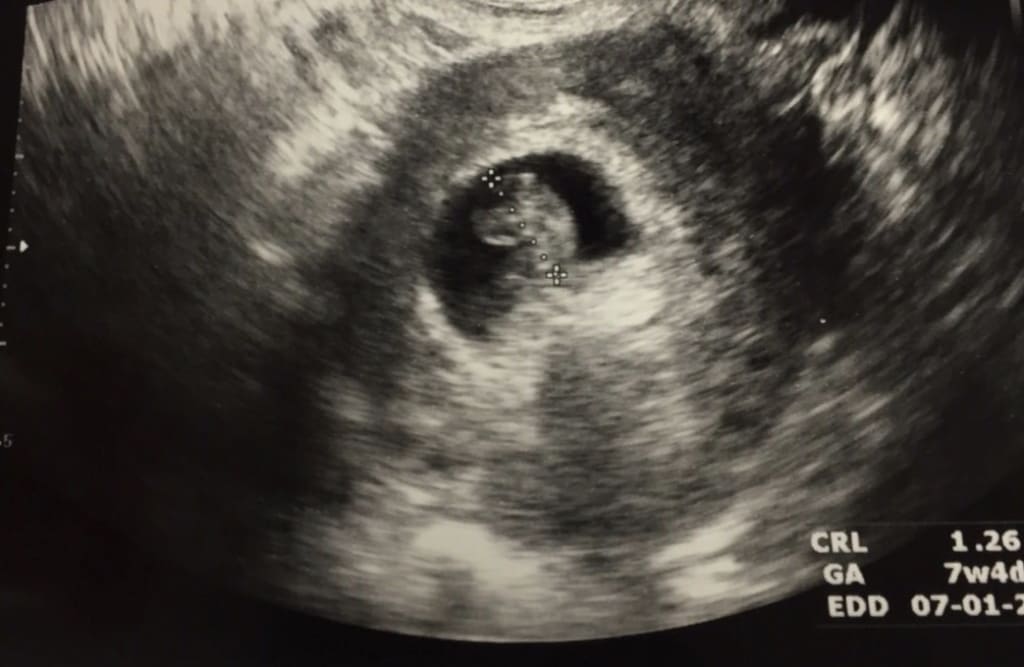

Three weeks later I went in for what I thought would be my eight week check up. It turns out you were measuring only at seven weeks but had a strong heartbeat. Hearing that little heartbeat put my mind at ease, if only for a short time. My doctor wanted me to come back in two weeks just so we could confirm your due date.